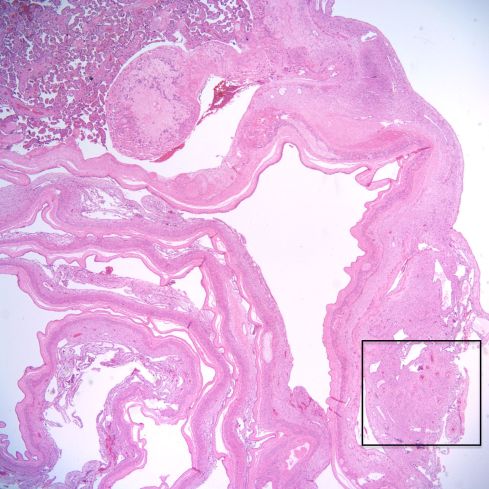

The spiral arteries may have a thickened media, which has been considered one form of decidual vasculopathy. I do not know of specific, quantified diagnostic criteria correlated with clinical income. Spiral arteries may appear thickened because of cell swelling, interstitial edema and interstitial fibrinoid material, as well as by smooth muscle hyperplasia10. The normal thickness may depend on gestation as well as nearness to areas of invasive cytotrophoblast (Figs 14-18).

Fig 17: This is a low power image of the membranes arising from the margin of the placenta. The rectangle shows a spiral artery in the membranes adjacent to the margin of the placenta. H&E 2x

Fig 18: This higher power of the above sample shows that the apparent thickened spiral artery is due to swelling from trophoblast-induced damage (circle). The trophoblast can be seen in the margin (arrow) H&E 10x